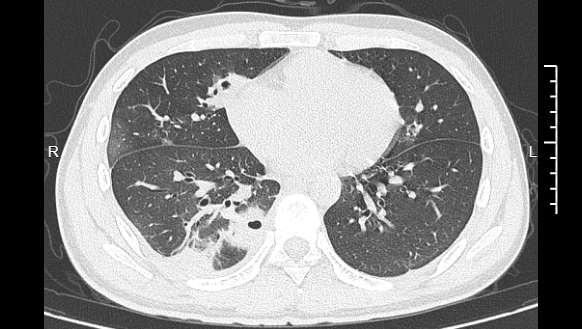

熬到第三天,小林已经烧到39℃,赶紧来到宁波大学附属第一医院就诊。接诊的丁群力主任医师一看他的症状,立刻安排了CT检查。结果显示:小林的肺里有十几个空洞,部分肺组织已经坏死,这是典型的血源性肺脓肿。

小林的CT影像显示肺里有多个空洞

这就意味着,当你挤压这个区域的痘痘时,会同时触发两个危险步骤:一方面,痘痘本身是毛囊发炎的产物,已经存在局部感染,挤压会直接破坏皮肤屏障,让痘痘里含大量细菌的脓液,接触到皮下毛细血管;另一方面,挤压的压力容易把这些细菌强行推进血管里。没有静脉瓣的阻挡,细菌可以顺着血液自由扩散,往上进入颅内,引发脑膜炎、脑脓肿等更凶险的疾病,往下顺着全身血液循环,跑到肺部、肝脏等器官,引发严重感染。像小林这样,当细菌跑到肺组织上后,就会开始疯狂破坏肺细胞,引发局部炎症。随着炎症加重,肺组织会逐渐坏死、液化,最终形成一个个空洞。